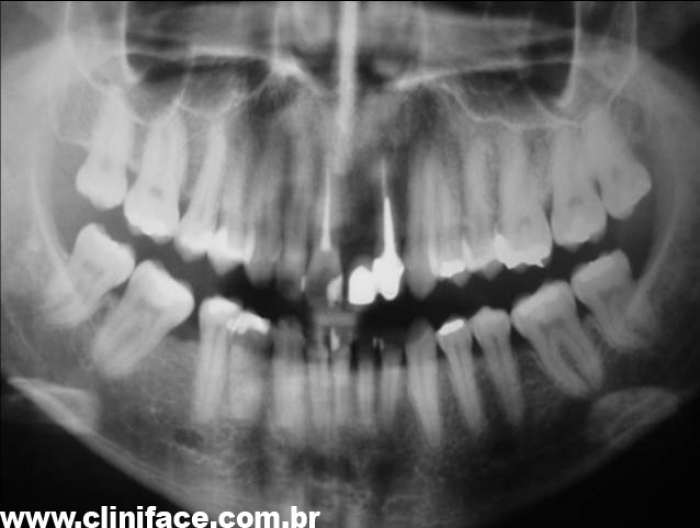

Rx inicial mostrando ausência do elemento 21